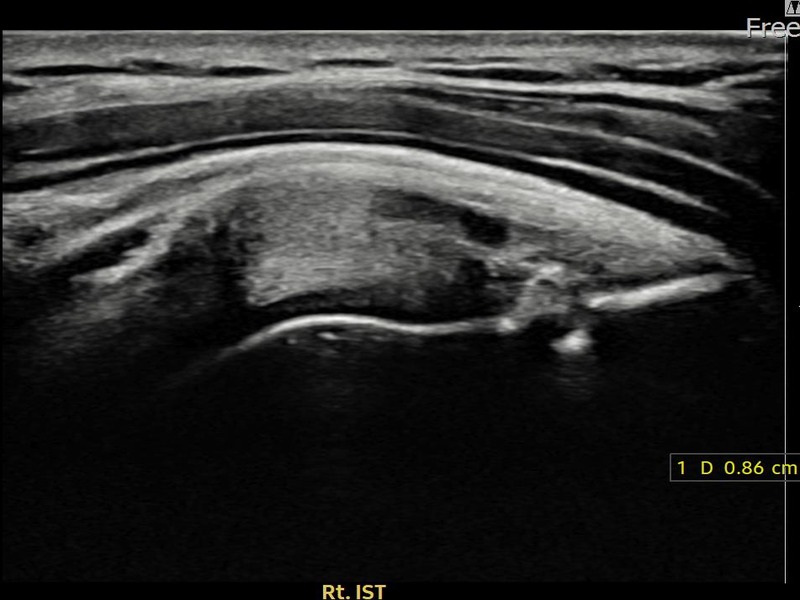

김ㅇㅇ님 · 우측 극하근건 관절면측 부분파열

우측 어깨 후방 통증과 팔을 바깥으로 돌릴 때 통증이 심해 내원하셨습니다. 초음파 검사에서 극하근건 관절면측 부분파열이 확인되었으며, 어깨인대 축소봉합술 후 힘줄 구조적 안정화가 이루어졌습니다.

김ㅇㅇ님 · 우측 극하근건 부착부 부분파열

우측 어깨 후방 통증과 외회전 시 심한 통증으로 내원하셨습니다. 초음파 검사에서 극하근건 부착부 부분파열이 확인되었으며, 어깨인대 축소봉합술 후 부착부 힘줄 연속성이 회복되었습니다.